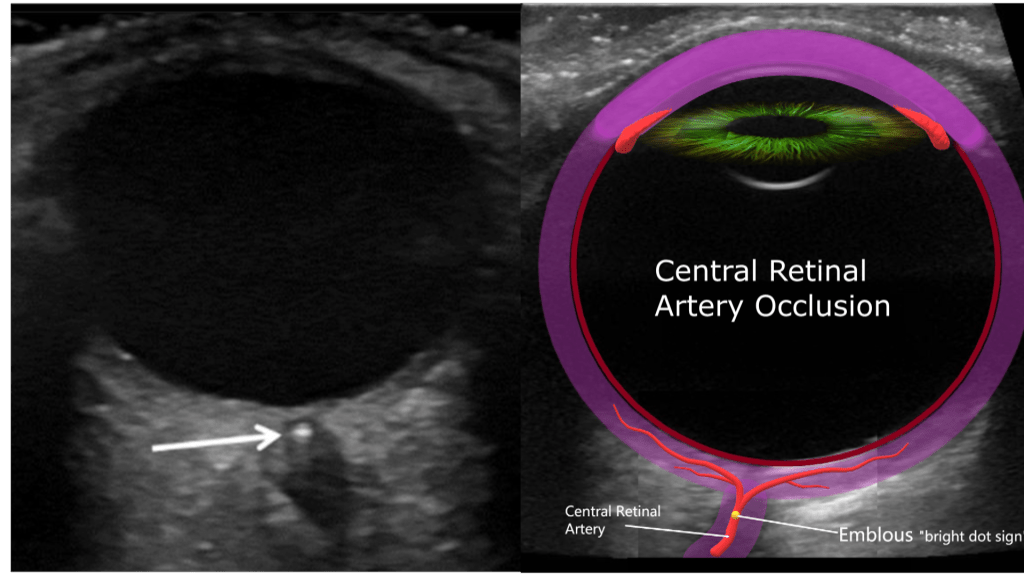

Central Retinal Artery Occlusion

Blockage of the central retinal artery usually due to an atherosclerotic thrombus (typically from an internal carotid artery plaque). Presents with sudden, painless, partial or complete monocular loss of vision. Also associated with giant cell arteritis. Patient describes “shade” or “curtain” coming down over entire visual field in the affected eye. Bilateral presentation is rare.

Sonographically you’ll encounter an echogenic foci posterior to the optic disc “bright dot sign” with lack of color or spectral flow distal to the thrombus